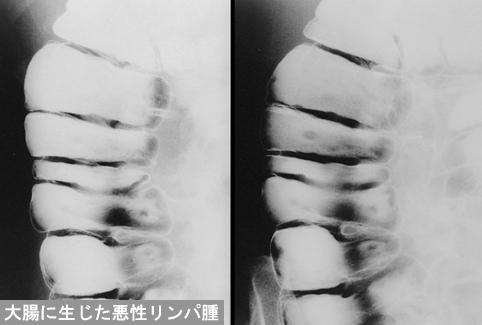

Posted by: Tokyo Pref., Cooperative study between National Cancer Center and Kyushu Cancer Center

ID:12201

[ Image ID:12201 ]